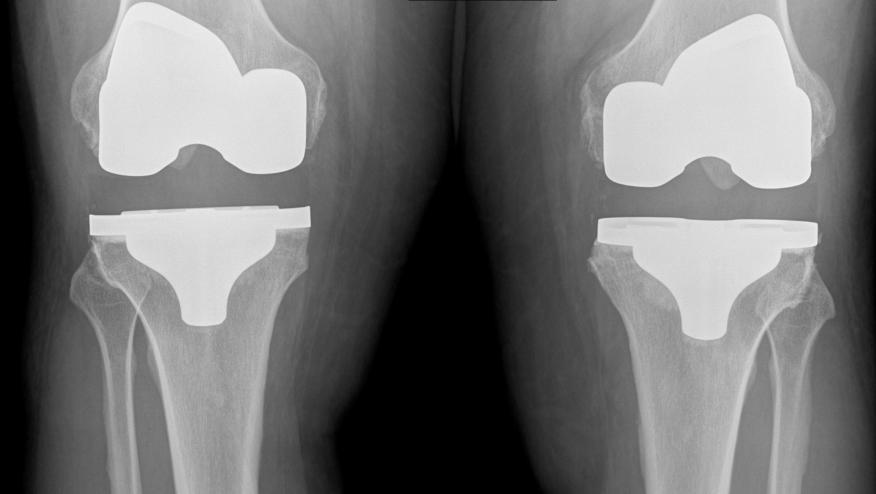

The global knee implants market was USD 8.4 billion in 2011, and it's forecasted to reach USD 15 billion in 2018, with compound annual growth rate of 8.64% during 2011 to 2018. The U.S. and Europe are the two big markets for knee implants, and both the countries enjoy more than 70% market share of global knee implants.